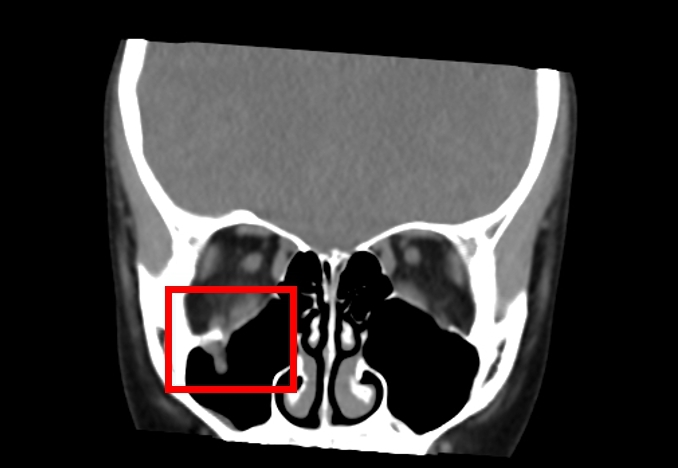

中山附醫口腔顎面外科邱昱瑋主治醫師指出,眼窩骨折常見於眼眶底部,多因直徑大於眼球的鈍器撞擊,例如棒球、拳頭或意外碰撞,造成較薄的眶底骨因力量傳導而破裂。兒童的骨頭相對柔軟,更容易發生所謂「線性爆裂性骨折」,這種骨折機制如同門片回彈復位,容易將眼眶內的肌肉或其他軟組織嵌頓在骨折縫隙中,導致複視及眼球運動受限。值得注意的是,兒童眼窩骨折往往不伴明顯瘀青或紅腫,家長容易掉以輕心,邱昱瑋醫師也提醒,若眼底肌肉因缺血受損而無法及時復位,可能造成永久性功能障礙,理想治療黃金時間僅有24至48小時,超過此期限後併發症風險將大幅提升。

中山附醫口腔顎面外科張芳語主治醫師補充,重建受損眼眶骨在臨床上挑戰重重,包括手術視野狹小、骨頭型態複雜、手術精準度要求高,以及術後疤痕與外觀重建的考量,透過精準的數位導航技術,醫師團隊能克服這些困難,幫助患者安全恢復功能與外觀,重拾自信與生活品質。洪珮瑄醫師則強調,對於兒童患者而言,手術精準度與微創性格外重要,不僅要恢復功能,更要兼顧未來面容發育的完整性;該起案例不僅展現數位導航手術在顏面骨折治療上的價值,也提醒家長與學校,即便外觀無傷痕,一旦出現眼球運動受限或複視症狀,應立即就醫,避免錯過黃金治療期。